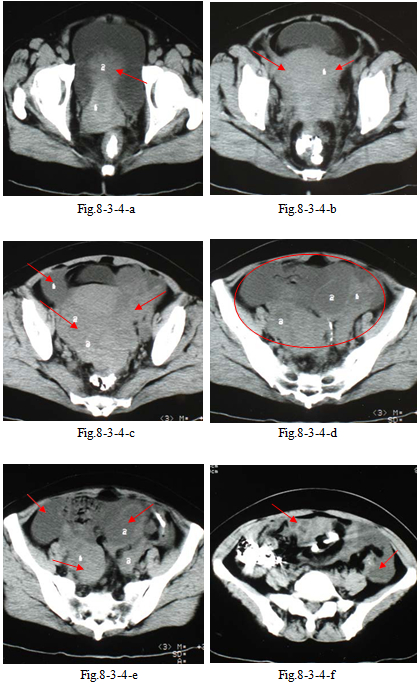

4.患者女性,49 岁。主诉:发现盆腔肿物1 周。妇科内诊:子宫附件可扪及儿头大小包块,活 动差。B 型超声:双附件实性及囊实性包块。CT 盆腔平扫(Fig.8-3-4-a~f)示:双侧卵巢囊实性恶性肿 瘤,与子宫界限不清,膀胱受压,肠间隙周围大量腹水。术后病理:双卵巢及右输卵管低分化癌,分别为腺癌,移行细胞癌,肉瘤样癌及黏液腺癌结构,直肠周围淋巴结 4/5 转移,右髂内外淋巴结 4/6 转移,左髂内外闭孔淋巴结3/5 转移。